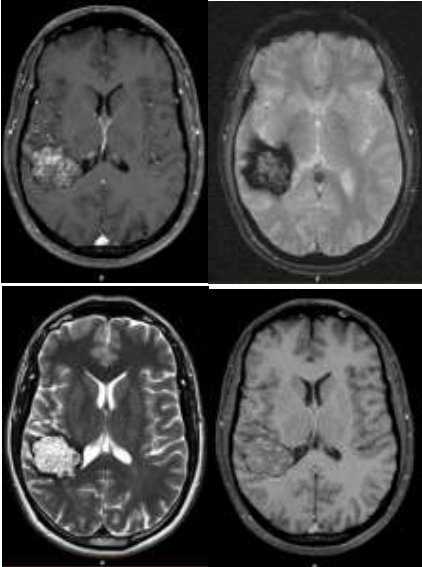

Paciente do sexo masculino, 40 anos, tabagista, apresentando episódio único de crise convulsiva tônico-clônica generalizada. Sem antecedentes de doença neurológica familiar. Encaminhado pelo neurologista assistente para investigação complementar com exames de imagem, que demonstrou os achados abaixo.

Baseado na história clínica e exames de imagem, assinale a alternativa correta.